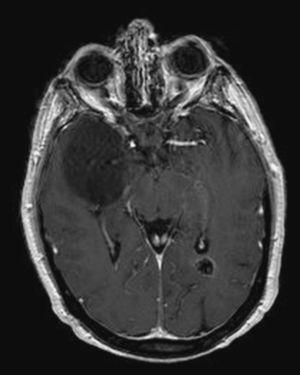

Ganglioglioma of the occipital lobe | Image | Radiopaedia.org

Ganglioglioma of the occipital lobe | Image | Radiopaedia.org from images.radiopaedia.org

Brain tumors are found in about 2% of routine autopsies. It is the part of the brain where visual information is processed. It sits posterior to the temporal lobe and parietal lobes, underlying the occipital bone and overlying the tentorium cerebelli.

Brain tumours can cause different symptoms depending on where they are in the brain. Tumors developing in the posterior aspect of the brain are termed occipital lobe tumors. The frontal lobe, the parietal lobe, the occipital lobe, and the temporal. It sits posterior to the temporal lobe and parietal lobes, underlying the occipital bone and overlying the tentorium cerebelli.